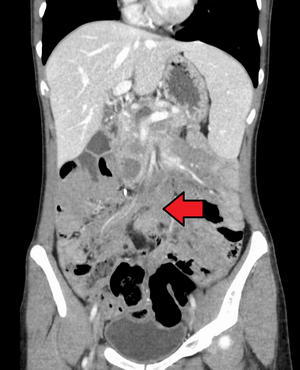

| ورم رباطي كما هو موضح في الاشعة المقطعية | |

الورم الليفي العدواني هو حالة نادرة تتميز بوجود أورام خبيثة . تنشأ الأورام الخبيثة من خلايا تسمى الخلايا الليفية ، والتي توجد في جميع أنحاء الجسم وتوفر الدعم الهيكلي والحماية للأعضاء الحيوية ، وتلعب دورًا مهمًا في التئام الجروح. تميل هذه الأورام إلى الحدوث عند النساء في الثلاثينيات من العمر ، ولكن يمكن أن تحدث لأي شخص في أي عمر. يمكن أن تكون إما بطيئة النمو أو خبيثة. ومع ذلك ، فإن الورم الليفي العدواني عدواني محليًا ويمكن أن يسبب مشاكل تهدد الحياة أو حتى الموت عندما يضغط على الأعضاء الحيوية مثل الأمعاء والكلى والرئتين والأوعية الدموية والأعصاب. معظم الحالات متفرقة ، لكن بعضها يرتبط بداء السلائل الغدي العائلي (FAP). ما يقرب من 10 ٪ من الأفراد الذين يعانون من متلازمة جاردنر ، وهو نوع من FAP مع ميزات خارج القولون ، لديهم أورام رباطية .[1]

يمكن تصنيف الأورام الرباطية على أنها خارج البطن أو جدار البطن أو داخل البطن (الأخير أكثر شيوعًا في مرضى FAP). يُعتقد أن الآفات قد تتطور فيما يتعلق بمستويات هرمون الاستروجين أو الاصابة / العمليات .[citation needed]